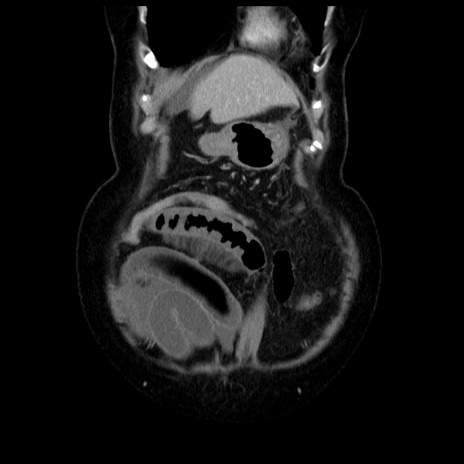

症例13(冠状断像)

【症例】70歳代女性

【主訴】腹痛、嘔吐

【現病歴】15時間程前(昨晩)より腹痛あり。今朝になっても症状の改善なく、嘔吐あり。腹痛も増悪あり、救急外来受診。

【既往歴】子宮癌全摘術後

【身体所見】意識清明、BP 121/72mmHg、P 74bpm、SpO2 100%(RA)、腹部:平坦・軟、腸雑音ほぼ聴取せず。下腹部・心窩部・臍左上に圧痛あり。反跳痛なし。

【データ】WBC 10600、CRP 0.15